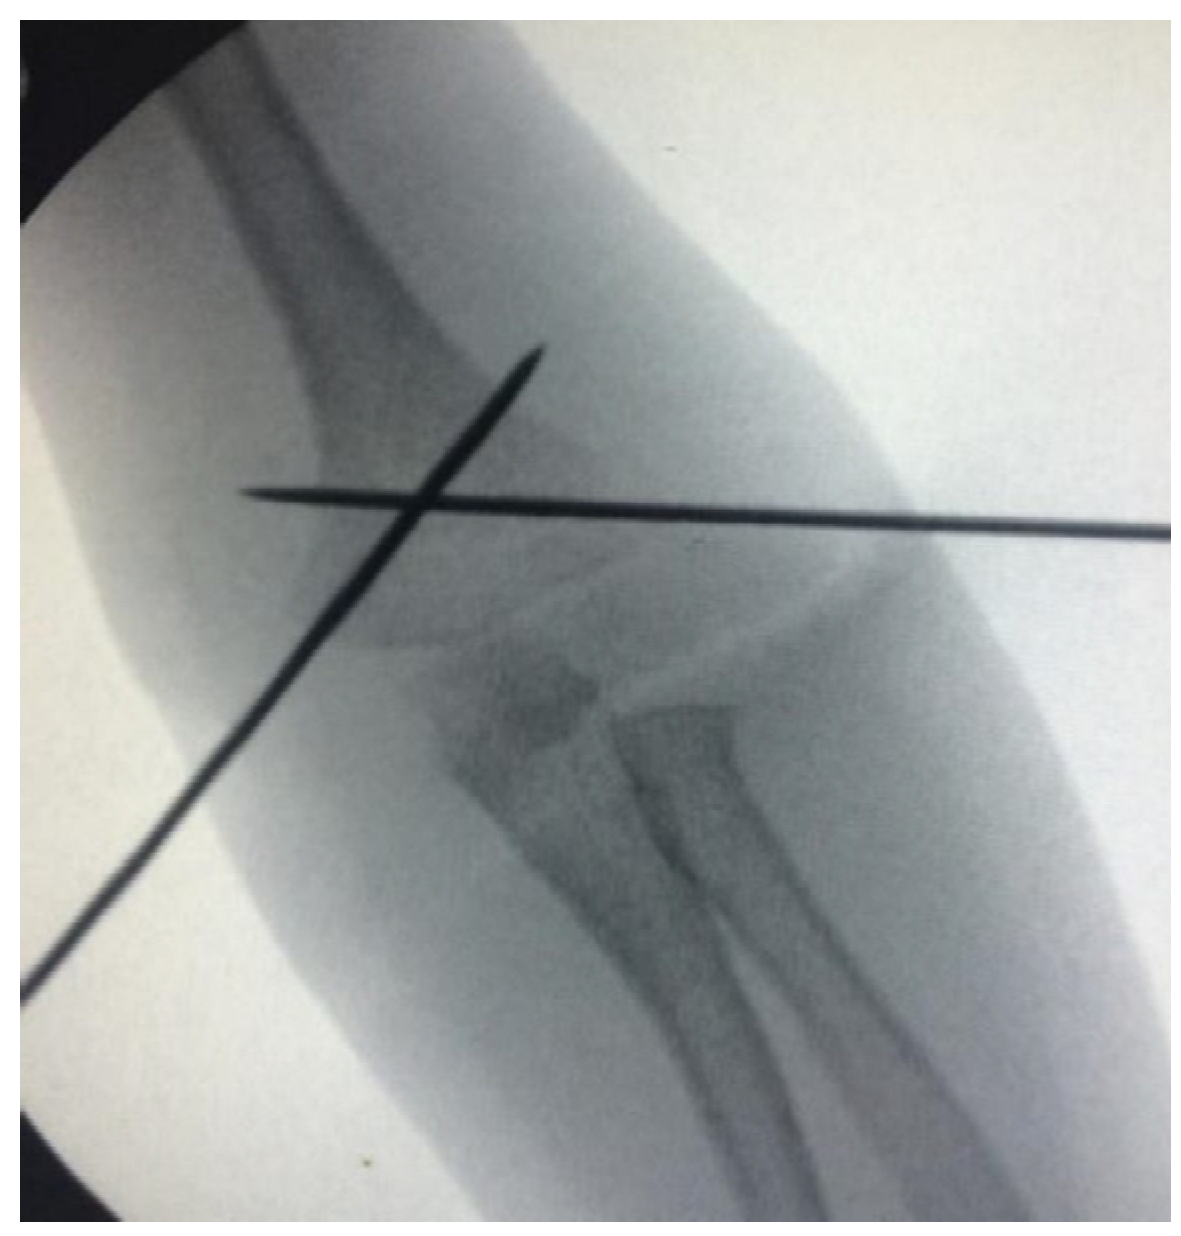

Extra Lateral Pin or Less Radiation? A Comparison of Two Different Pin Configurations in the Treatment of Supracondylar Humerus Fracture

2. Materials and Methods